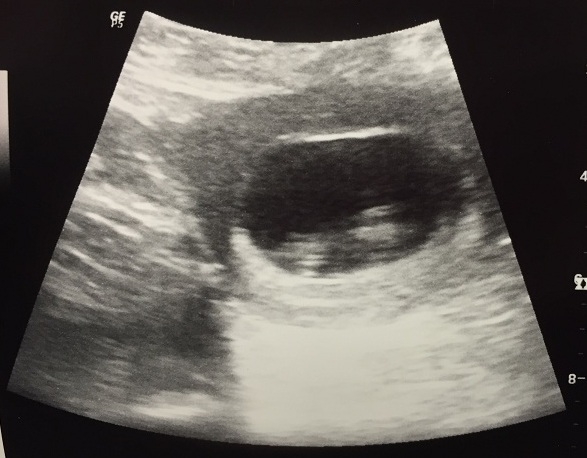

I've been feeling the baby move a lot more lately. It's not flutters anymore but little bumps. I absolutely love it. However, when I go a day or two without feeling it as much I freak out. My doc assures me that it's normal. I have my anatomy scan today. I am so excited. I haven't seen this little guy since he was this big!